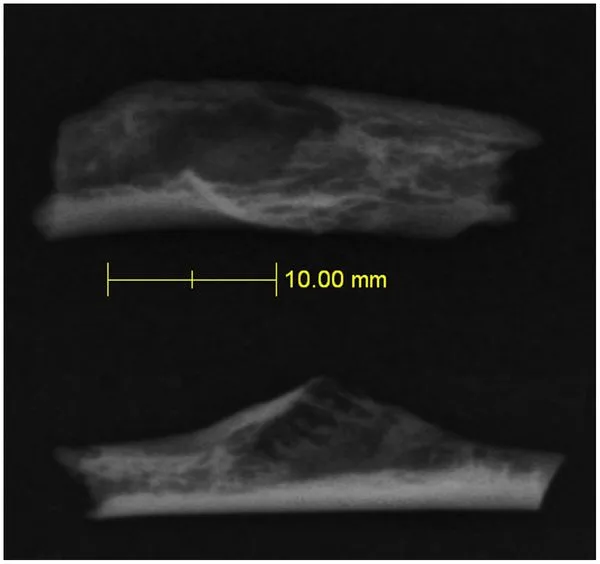

CT สแกนช่องว่างมีขนาด 10 มม.

CT สแกนกระดูกซี่โครงแสดงช่องว่างที่เกิดจากเนื้องอก

ฟอสซิลถูกขุดขึ้นจากแหล่งโบราณคดีที่สำคัญ ซึ่งให้หลักฐานกระดูกมนุษย์โบราณประมาณ 900 ชิ้น พร้อมกับเครื่องมือหิน และได้รับการวินิจฉัยว่าเป็นมะเร็งโดยนักรังสีการแพทย์ซึ่งใช้รังสีเอกซ์และเครื่องซีทีสแกน (CT scans) ตรวจวิเคราะห์ หากแต่ซี่โครงที่เป็นมะเร็งนั้นไม่ได้เป็นตัวอย่างที่สมบูรณ์ ดังนั้น จึงไม่อาจประเมินผลกระทบจากมะเร็งต่อสุขภาพโดยรวมได้